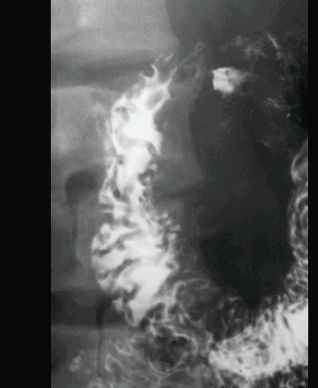

UCHYŁEK PRZEŁYKU

KONTRAST DO GOPP